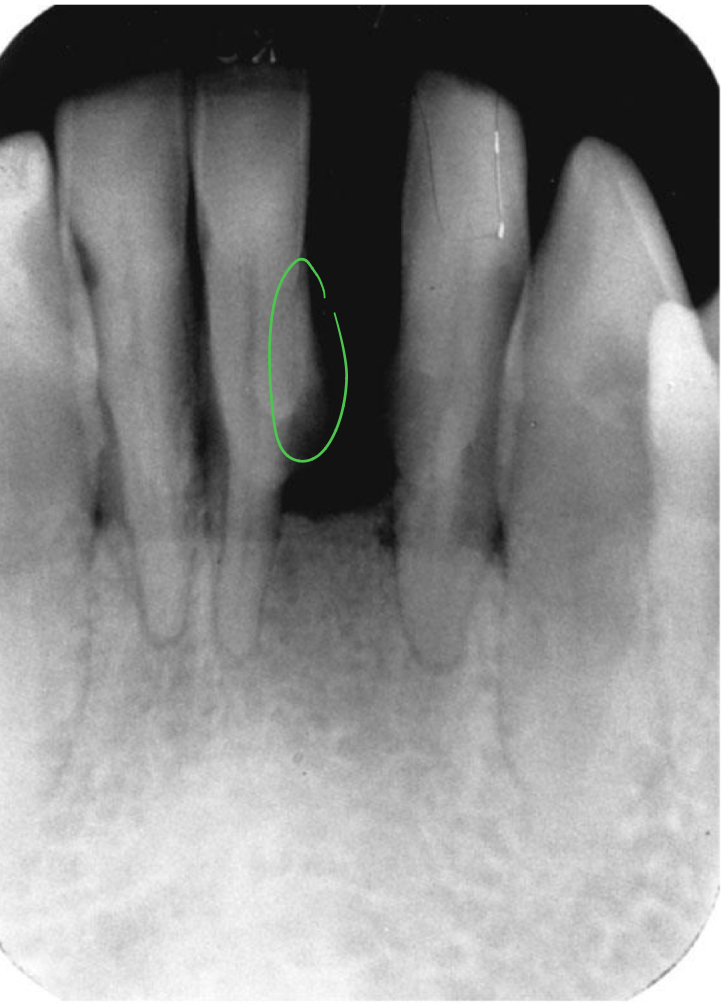

Bone loss

Difference between the physiologic bone level and height of remaining bone

Horizontal vs vertical

Horizontal bone loss

Distribution of bone loss

Localized vs generalized

Localized bone loss

Occurs in isolated areas less than 30%